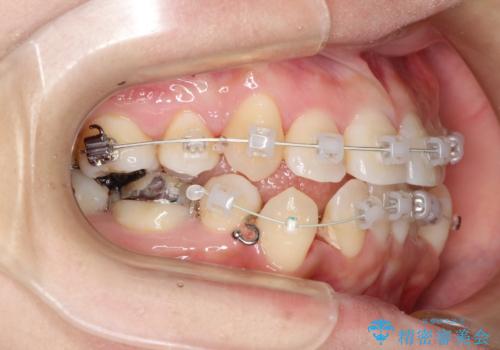

- 審美装置(ブラケット:白/ワイヤー:白)

スペースの不足量が著しく、上下左右の抜歯を伴うワイヤー矯正にて治療を行いました。

抜歯によるスペースを利用し、強いがたつきの改善を行いました。

また、左上の奥歯に関して親知らずの1つ手前の歯の状態が悪かったため、その歯は抜歯をし親知らずを利用して噛み合わせを作りました。